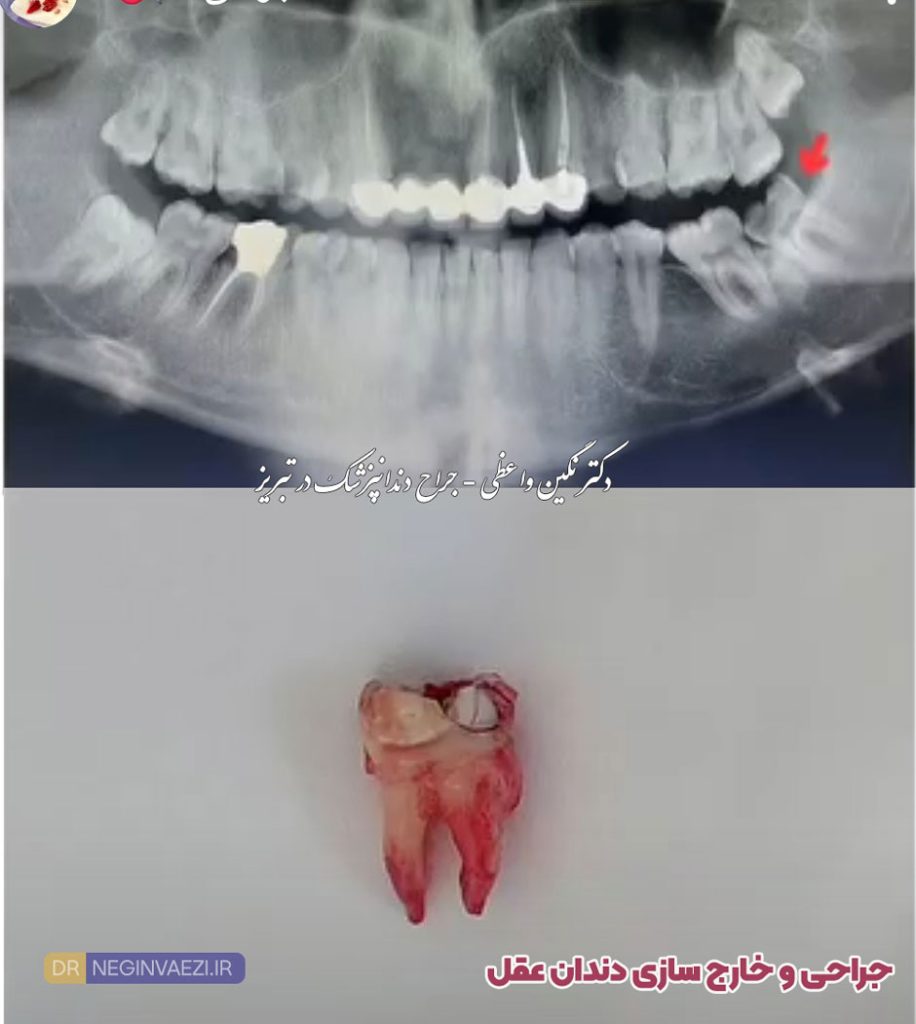

عکس جراحی دندان عقل فک پایین

عکس جراحی دندان عقل نیمه نهفته

عکس کشیدن دندان عقل

آیا برای جراحی دندان نیاز به عکس رادیوگرافی می باشد؟

بله! دندانپزشک قبل از هرگونه جراحی اعم از دندان عقل یا ریشه دندان، عکس رادیوگرافی تجویز خواهد کرد و پس از آن اقدام به کشیدن و یا جراحی خواهد نمود.